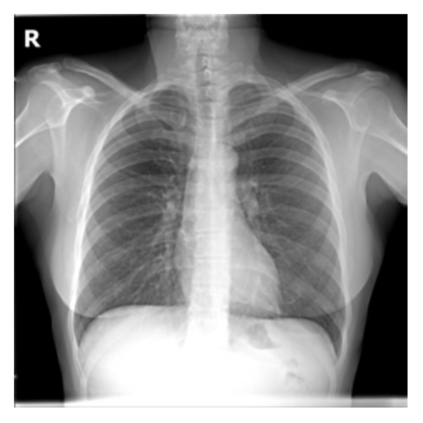

The evaluation of infectious disease processes on radiologic images is an important and challenging task in medical image analysis. Pulmonary infections can often be best imaged and evaluated through computed tomography (CT) scans, which are often not available in low-resource environments and difficult to obtain for critically ill patients. On the other hand, X-ray, a different type of imaging procedure, is inexpensive, often available at the bedside and more widely available, but offers a simpler, two dimensional image. We show that by relying on a model that learns to generate CT images from X-rays synthetically, we can improve the automatic disease classification accuracy and provide clinicians with a different look at the pulmonary disease process. Specifically, we investigate Tuberculosis (TB), a deadly bacterial infectious disease that predominantly affects the lungs, but also other organ systems. We show that relying on synthetically generated CT improves TB identification by 7.50% and distinguishes TB properties up to 12.16% better than the X-ray baseline.